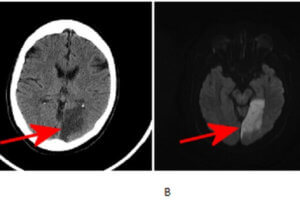

Dense MCA sign in R hemisphere

Early Signs of Stroke on CT

Despite its poor sensitivity for detecting embolic strokes, head CT scan remains the initial imaging modality in the work up of suspected acute stroke. The rationale is to initially rule out hemorrhagic... Read more »